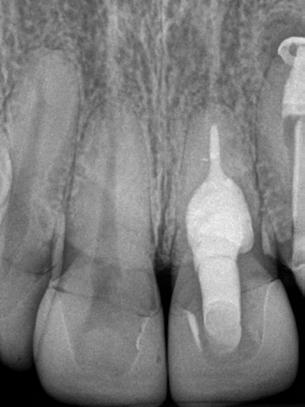

Caso clínico

Paciente del género femenino, 44 años de edad, asistió al consultorio para realizar el retratamiento endodóntico del diente 22. Hemos hecho la radiografía inicial para evaluar el diente 22 y nos encontramos con una imagen radiolúcida en forma de globo, caracterizando una reabsorción radicular interna en el diente 21. Hemos hecho, entonces, una nueva radiografía para evaluar el diente 21 (Figura 1).

Figura 1 - Radiografia inicial

Durante la anamnesis la paciente relató haber sufrido un cabezazo del hijo hace dos años. El examen clínico reveló presencia de faceta de porcelana en el diente 21, prueba de sensibilidad pulpar positiva, ausencia de sintomatología y ausencia de alteraciones en la mucosa gingival. Solicitamos una tomografía computarizada cone beam (Figuras 2, 3 y 4) para confirmar el diagnóstico, evaluar si la reabsorción era comunicante o no y para estudiar la estructura dental radicular remanente.

Después del análisis clínico, radiográfico y tomográfico, se estableció el diagnóstico de reabsorción radicular interna, sin comunicación externa, lo que hace el pronóstico más favorable.

Se inició la terapia endodóntica del diente 21. Después del acceso, el conducto fue irrigado con Hipoclorito de Sodio al 5%, seguido de EDTA al 17%, ambos con PUI y Easy clean. A través del uso del microscopio operatorio, fue posible visualizar la extensión de la cavidad reabsortiva (Figura 5). Durante la preparación químico-mecánica hicimos una irrigación abundante con sustancias químicas auxiliares con capacidad solvente orgánica efectiva y punta de ultrasonido esférica para remover y diluir el tejido pulpar remanente.

A continuación, el canal fue rellenado con una pasta de Hidróxido de Calcio PA (Pro-Análisis) con suero fisiológico (Figura 6) para cauterizar químicamente el tejido, que quizá todavía estaba presente en la cavidad y para promover la necrosis de todas las unidades osteo remodeladoras en función de su alto pH y alcalinización del medio cesando, de esa forma, la actividad clástica.

Figura 6 - Medicación intraconducto

En la segunda sesión, 15 días después, realizamos la obturación convencional del tercio apical del canal con gutapercha, llenado de la cavidad reabsortiva con BIO-C ® REPAIR (Angelus, Londrina - Brasil) (Figura 7, 8 y 9), condensándolo contra las paredes con condensadores específicos y bolita de algodón humedecida y realizamos el sellado coronario con resina.